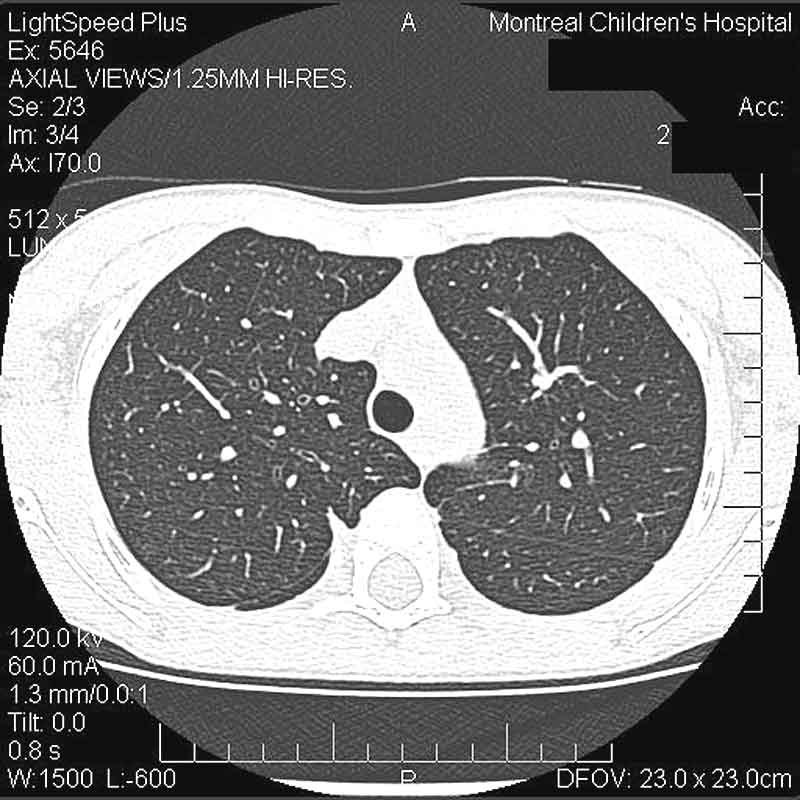

At 6 weeks follow up a limited High Resolution CT was performed. There is complete normalization of his previous disease with no evidence of fibrosis.

Enlarge the CT on the LEFT, enlarge the CT on the RIGHT.